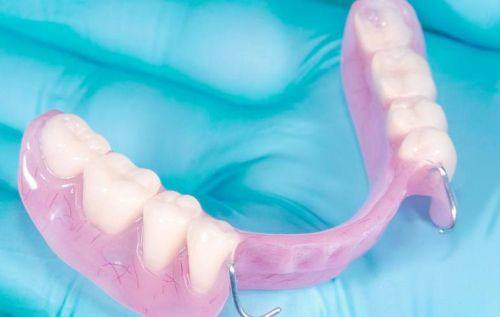

14. 活动义齿:1000-3000元

15. 义齿修理:100-500元